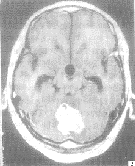

2.2 桥脑小脑角听神经瘤3例 当地CT上颅后窝伪影较多(图3),其中2例第四脑室结构不清,1例第四脑室形态尚可,但一侧桥脑小脑角隐约可见占位影,并有第三脑室和侧脑室明显扩大。本院MR显示3例均为较大的听神经瘤,T1W呈稍低信号,T2W呈高信,有明显不均匀增强。

图3 右侧桥

脑小脑角听神经瘤。颅后窝伪影干扰